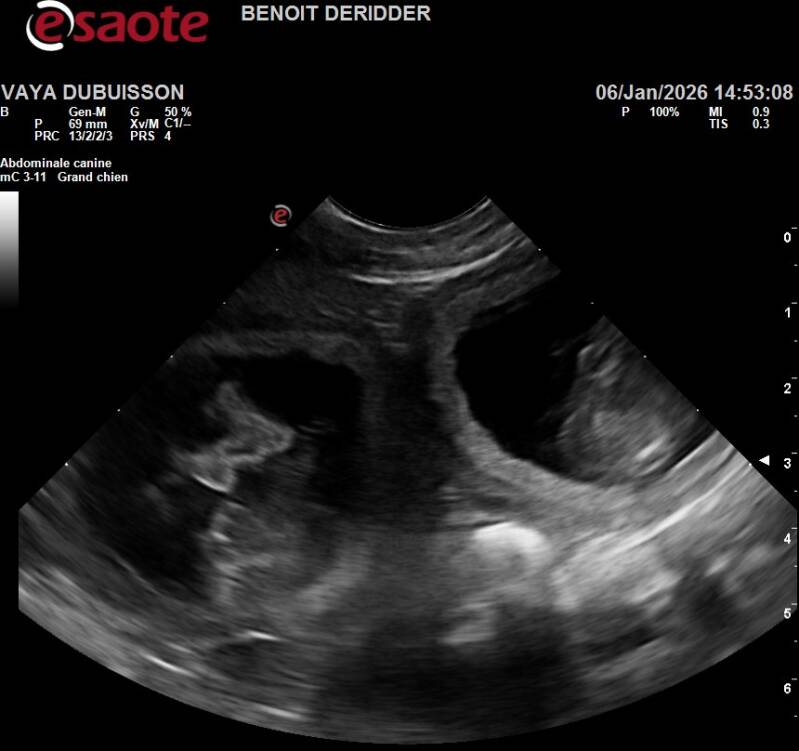

Ce 06/01/2026, je suis allée chez le veto pour une échographie afin de confirmer la gestation de Vayana mais à coup sûr, j'en étais convaincue parce que Vasco & Vayana c'est magique, je dirai même plus une alchimie, ils ne leur suffit qu'un seul accouplement pour que la magie opère..

Ça y est, Benoît commence à passer sur le ventre de Vayana et nous pouvons apercevoir sur l'écran jouxtant en hauteur de la table quelque chose ou ressemble à ... Oui oui dit-il avec un sourire joviale, Vayana a remis ça, on en compte approximativement 7 mais connaissant la demoiselle, nous ne serions pas surpris d'en avoir 10...